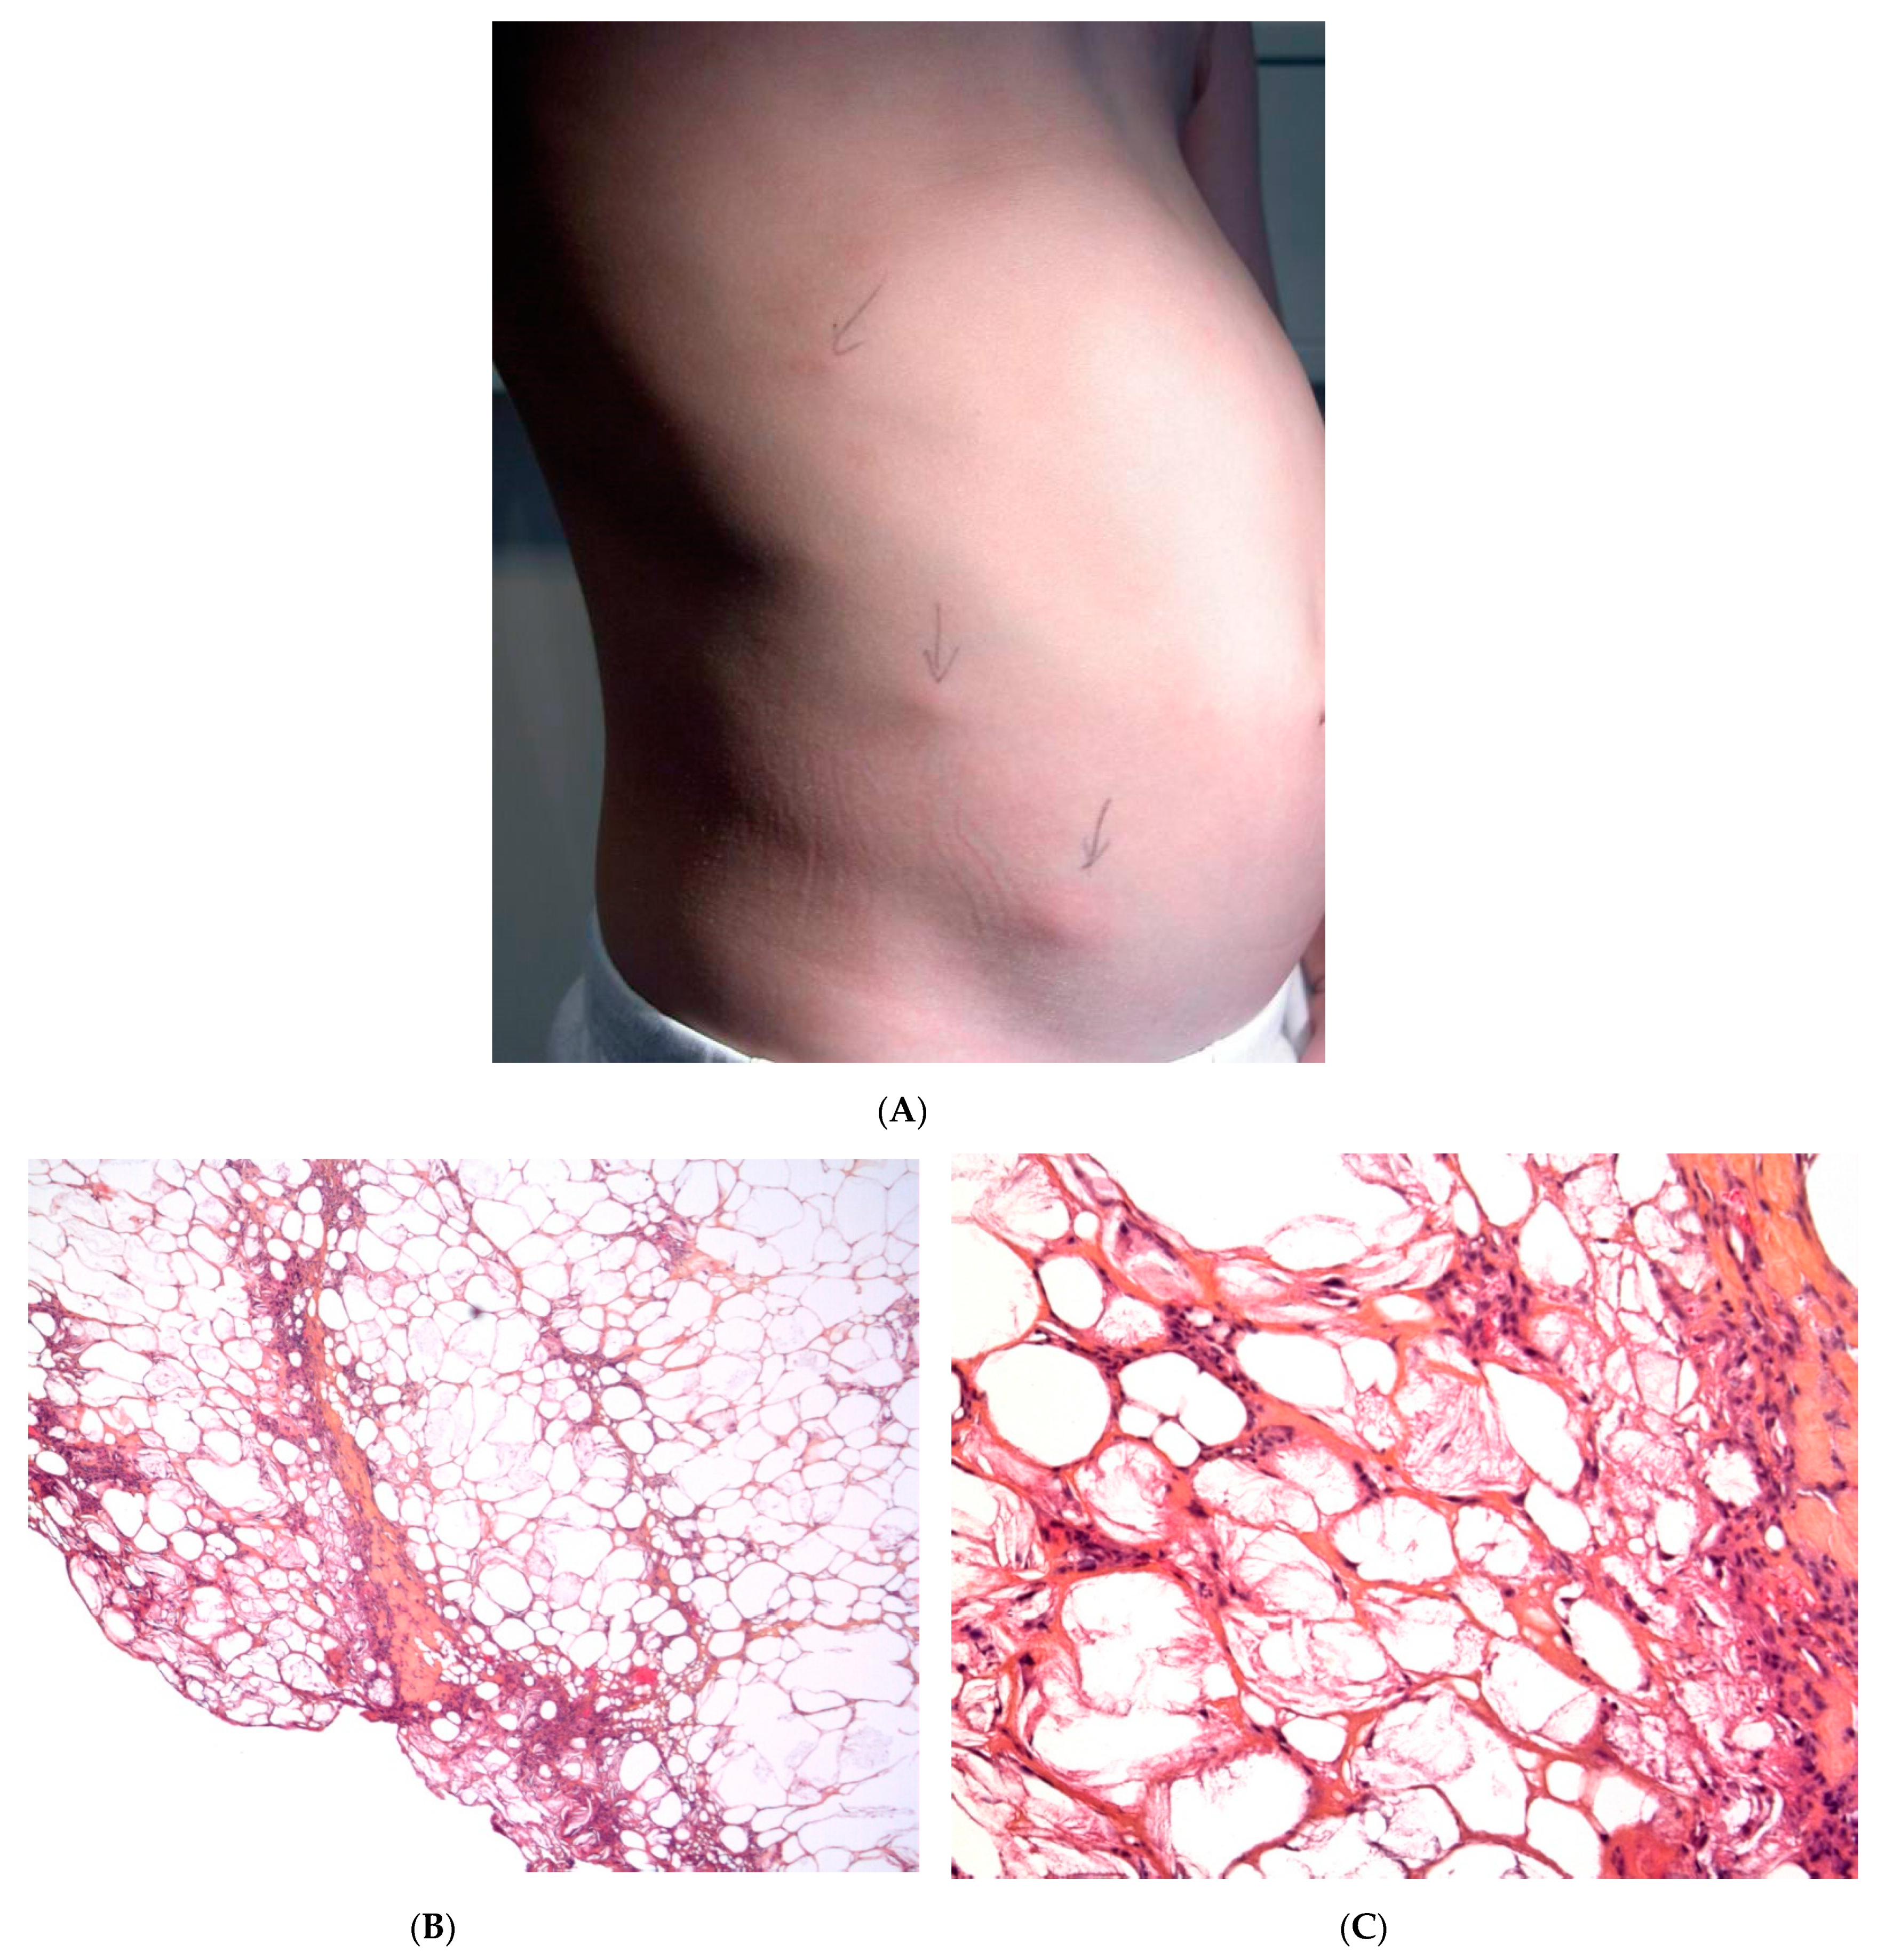

2.2. Post-Steroid Panniculitis

Post-steroid panniculitis is a very rare form of lobular panniculitis that has only been observed in children in whom systemic treatment with high-dose corticosteroids has been suddenly withdrawn. One to ten days after this withdrawal, erythematous subcutaneous nodules measuring 0.5 to 4 cm appear on the cheeks, the arms, or trunk (Figure 2A). The nodules may ulcerate, with scarring. The sudden withdrawal of corticosteroids might cause an increase in the saturated:unsaturated fatty acid ratio, and thus, crystal formation.

Figure 2.

Post-steroid panniculitis. (A) Clinical presentation: subcutaneous nodules with overlying erythema. (B) Histopathologic features of post-steroid panniculitis: mostly lobular panniculitis with an inflammatory infiltrate of foamy histiocytes involving the fat lobules (original magnification ×40). (C) Needle-shaped clefts (original magnification ×400).

Histopathology

The findings are similar to SFN: a mostly lobular panniculitis features an inflammatory infiltrate of foamy histiocytes, with lymphocytes in the fat lobules. Some of the histiocytes show needle-shaped clefts in the cytoplasm (Figure 2B,C). In most cases, the inflammation is less intense and the crystals are less numerous than in SFN [11].